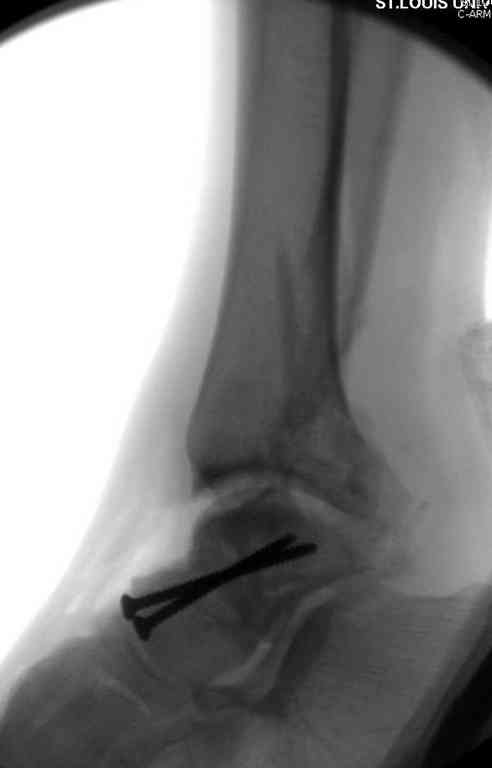

Второй случай прооперирован вчера.

10 дней назад поступил с открытым повреждением медиальной лодыжки и переломо вывихом таранной кости. Ургентно сделана репозиция с наложением наружного фиксатора + Irrigation&Debridment.

Вчера провели фиксацию.

Из-за многооскольчатости дистальной части малоберцовой, где невозможно было провести фиксацию шурупами, перелом зафиксирован подпирающей пластиной, которая должна служить дополнением отсутствующей дистальной части малоберцовой (lateral cortex substitute).

Для стабильности два шурупа на синдесмоз.

Медиальную рану с приближенными краями продолжаем вакуумировать (KCI). Наружный фиксатор оставлен на пару недель, надеюсь, небольшая рана будет гранулировать и закроется без кожной пластики. Фиксация медиальной ложыжки не планируется.